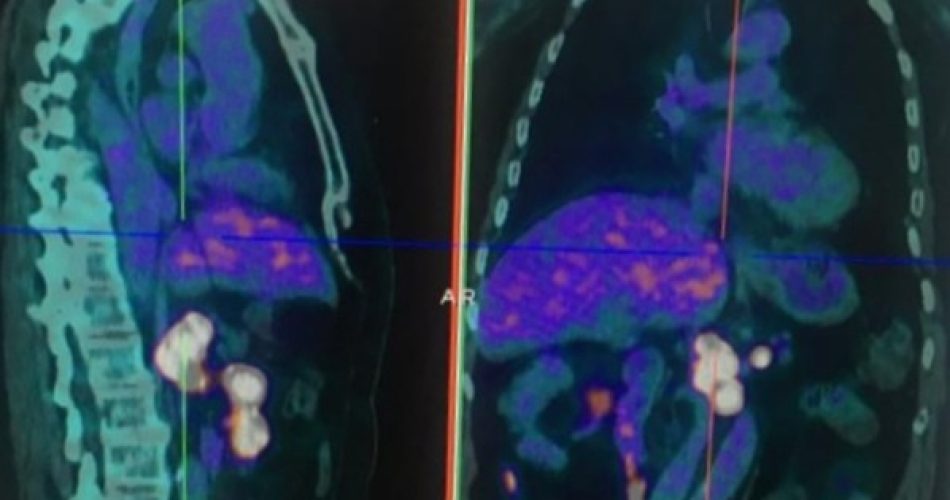

Tumori neuroendocrini: eseguita a Barletta per la prima volta in Puglia la prima Pet con Gallio 68

Un passo avanti importante nello studio di tumori neuroendocrini all’Ospedale Dimiccoli di Barletta: per la prima volta nella Regione Puglia nella unità operativa diretta dal dottor Pasquale Di Fazio è stata eseguita una Pet (Tomografia ad emissione di Positroni) con Gallio 68 per lo studio e la diagnosi del tumore del neuroendocrino, patologia rara di cui sino a poco tempo fa si conosceva ben poco.

“Questo tipo di tumore non ha una sede elettiva e si può sviluppare in qualsiasi parte del nostro corpo – dice Pasquale Di Fazio – le sedi maggiormente interessate sono intestino, polmone, fegato e pancreas. Avere quindi una metodica diagnostica accurata come la Pet in abbinamento ad un radiofarmaco come il ­Gallio 68, ci permette di individuare correttamente la patologia, di studiare le progressioni di malattia e quindi le metastasi e soprattutto ci permette di orientare la terapia e di comprendere se è utile una terapia con farmaco radioattivo o meno”.

“L’avvio di questa attività ci permette di affermare che – continua Di Fazio – siamo l’unico centro in Puglia a poter garantire diagnosi e cura attraverso l’esame diagnostico e le attività della Radioterapia metabolica dove è possibile somministrare il farmaco in fase di terapia. Stiamo parlando di “teragnostica”, cioè di diagnosi e terapia combinate per una medicina sempre più personalizzata. Garantiremo la massima collaborazione a tutte gli oncologi e gli endocrinologi della Regione che si occupano della diagnosi e della cura di questo particolare tumore”.